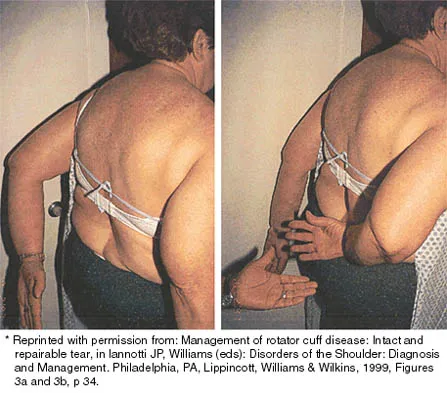

A 43-year-old bus driver sustains a hyperextension injury to her arm and shoulder 4 months after undergoing an open Bankart repair. Examination reveals increased external rotation, anterior shoulder pain, and internal rotation weakness. Her examination also reveals the findings shown in Figure 44. What is the most likely diagnosis?

Explanation